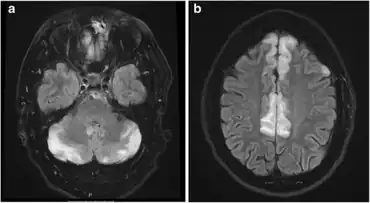

Diagnostic methods for hypertensive encephalopathy include physical examination, blood pressure measurement, blood sampling, ECG, EEG, chest X-ray, urinalysis, arterial blood gas analysis, and imaging of the head (CAT scan and/or MRI). Since decreasing the blood pressure is essential, anti-hypertensive medication is administered without awaiting the results of the laboratory tests. Electroencephalographic examination detects the absence of alpha waves, signifying impaired consciousness. In people with visual disturbances, slow waves are detected in the occipital areas.